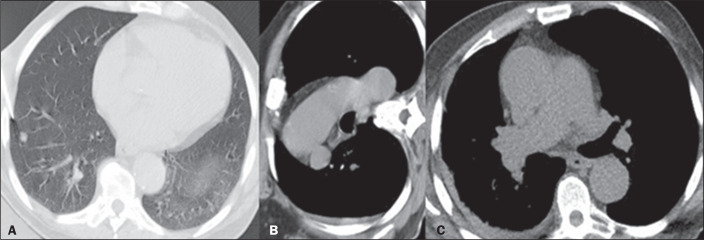

Objective: To assess the diagnostic success rate and complications of computed tomography (CT)-guided percutaneous biopsy in pulmonary nodules < 10 mm in diameter.

Materials and methods: This was a retrospective, single-center study involving the review of medical records, images, and chest CT reports related to 115 patients who underwent percutaneous CT-guided biopsy of < 10 mm pulmonary nodules between July 2015 and January 2019.

Results: Nodule diameter on the longest axis ranged from 4 mm to 9 mm, with a mean size of 7.7 mm. The mean age of the patients at the time of the procedure was 61 years, and 54.7% were women. Of the 115 nodules evaluated, 77 (67.0%) were solid and 55 (47.8%) were located in the lower lobes. The mean distance traversed by the needle in the lung parenchyma was 20 mm (range, 0-70 mm), and, in most cases, the biopsy was not performed with the patient in the biopsy-side-down lateral position. The diagnostic success rate was 93.0%. The most common complications were alveolar hemorrhage (in 36.5% of cases) and pneumothorax (in 24.3%).

Conclusion: The data suggest that CT-guided percutaneous biopsy of < 10 mm pulmonary nodules has a high diagnostic success rate and an acceptable rate of complications.